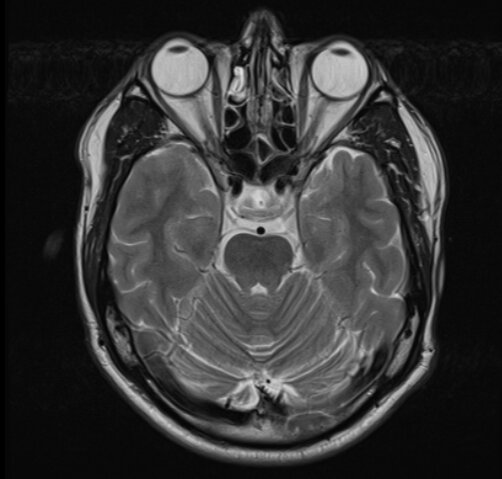

Что можно увидеть на МРТ?

Все ткани организма. Но, в отличие от КТ, видимость ткани зависит от содержания в ней жидкости (точнее атомов водорода). Т.е. очень хорошо видно:

- глаза;

- нервную систему;

- мышцы;

- хрящевую ткань;

- различного рода отеки (в т.ч. трабекулярный отек костей, который на КТ не виден);

- в ангиорежиме (сосудистом) можно увидеть ход движущейся крови без использования контрастных веществ - а значит контуры сосудов;

- кости тоже видно, но точный диагноз по костной патологии по МРТ поставить бывает затруднительно, поэтому в дополнение доктор может назначить КТ.